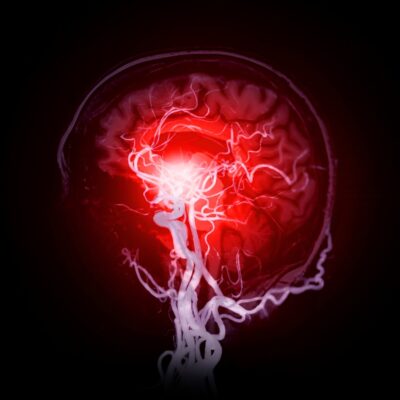

Neurosurgery is a specialized medical field focused on the diagnosis and surgical treatment of disorders affecting the brain, spine, and peripheral nerves. At Vijetha Hospital, we manage a wide spectrum of neurological conditions, from life-threatening brain injuries to minimally invasive spine procedures and peripheral nerve surgeries. Our goal is to restore function, relieve pain, and improve quality of life for our patients through precise and compassionate care.

Surgical removal and post-operative care for brain tumors. - Cerebrovascular Diseases (Aneurysms, AVMs, Stroke)

Timely surgical interventions for vascular abnormalities in the brain improve survival and recovery. - Head Injuries/Trauma

Small incision procedures that reduce post-operative pain and shorten hospital stays. - Cerebral aneurysm Clipping & Coiling

Techniques to repair weakened blood vessels in the brain and prevent rupture. - Spinal Fusion